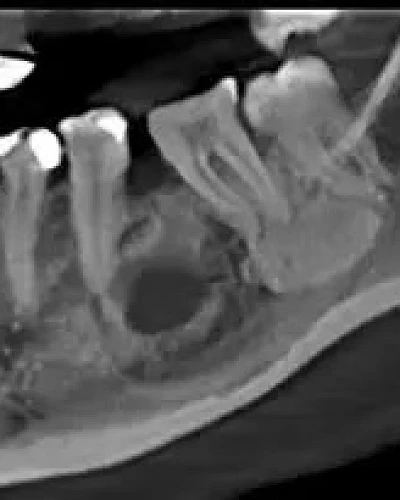

Quistectomías Dentales

Proteja su mandíbula e integridad dental con nuestros procedimientos expertos de quistectomía. Los quistes orales, si no se tratan, pueden desplazar los dientes y debilitar las estructuras óseas. Nuestro enfoque quirúrgico implica la eliminación precisa del quiste y su membrana, seguida de una limpieza profunda de la cavidad. Nos centramos en técnicas mínimamente invasivas y, cuando es necesario, injertos óseos avanzados para asegurar una curación rápida.